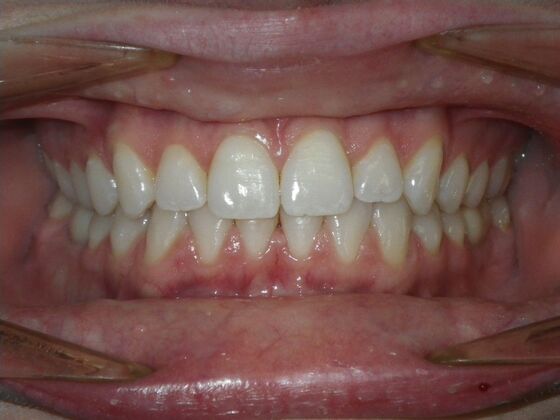

Invisalign: Case 17

This patient was an awesome dental assistant for our practice and we were all very sad when she had to move closer to her home. She was very interested in correcting some minor spacing and rotations in her upper and lower anterior teeth and to decrease her overbite as well.Treatment took about 12 months, but we were pleased with the results and fabricated clear invisalign vivera retainers. We are still hoping one day she will return to be with us again.